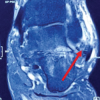

Magnetic resonance imaging (MRI) revealed a lesion with an irregular surface, a cartilage cap of 2.5 cm, local invasion into rectus femoris and vastus medialis, and calcific rings and arcs within the lesion on computed tomography (CT) correlation (Figs. 3, 4, 5, 6).

Woertler et al. conducted a MRI pictorial review of 2600 cases with symptomatic osteochondroma and found that a cartilage thickness of 2 cm in adults and 3 cm in children is suspicious of malignant transformation [8]. Stacy et al. in a pictorial essay, found that an increased thickness of the cartilage cap was suggestive of malignant transformation [9]. Ahmed et al. conducted a study on 107 patients suffering from secondary chondrosarcoma arising from osteochondroma. They found an irregularity in the surface, areas of lucency, and inhomogeneous mineralization within the tumor and surrounding soft tissue was characteristic of malignant transformation [10]. Our case exhibited a cartilage cap of <3 cm, irregular surface, invasion of the rectus, and vastus medialis, and on CT correlation, calcific rings and arcs were observed with scattered irregular calcifications.

Hence, in our case, the size of the cartilaginous cap which was <3 cm was indicative of a benign lesion but the rest of the MRI and CT features of the lesion were in favor of malignant transformation making it a borderline case for suspicion of malignancy. The histopathology post-wide excision was indicative of a benign osteochondroma. The patient underwent a PET scan post-surgery and will be on regular follow-up to look for local recurrence or other signs of metastasis.